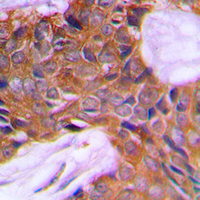

IHC (Immunohiostchemistry)

(Immunohistochemical analysis of PAGE3 staining in human prostate cancer formalin fixed paraffin embedded tissue section. The section was pre-treated using heat mediated antigen retrieval with sodium citrate buffer (pH 6.0). The section was then incubated with the antibody at room temperature and detected using an HRP conjugated compact polymer system. DAB was used as the chromogen. The section was then counterstained with haematoxylin and mounted with DPX.)